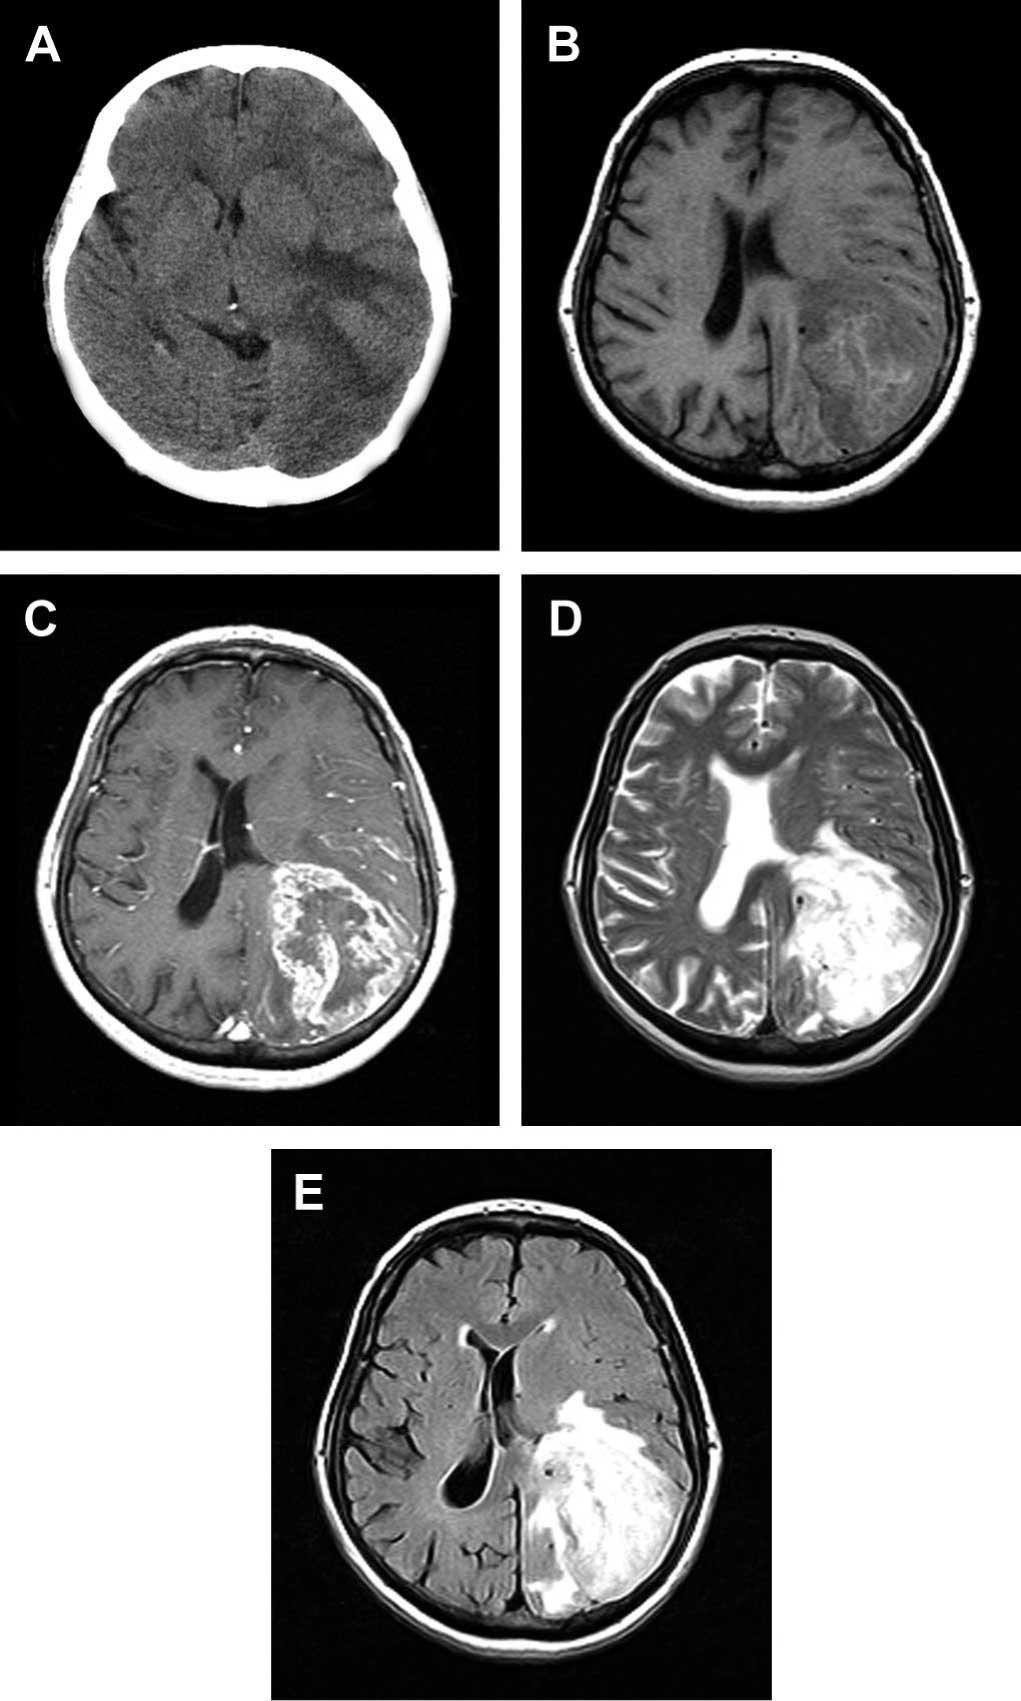

Коли лунають слова «набряк головного мозку», більшість з нас розуміє, що це — серйозно. Але справжні наслідки цієї патології можуть бути настільки багатогранними, що вони часто стають несподіванкою, навіть для досвіду лікарів.

- Інсульти — несподівані звуження та розширення судин. Ось така гра в рулетку.

Кров’яний потік та об’єм: як усе це взаємодіє?

Ну, насамперед, говоримо про те, як важливо підтримувати нормальний кров’яний потік в голові. Це не просто метафора, а справжнє питання життя і смерті. Буквально. І тільки трішки — образно.

Мозок — це, насправді, та ще машина. Він сильно залежить від життєвоважливих умов… і якщо щось йде не так, наслідки можуть бути відчутні одразу.